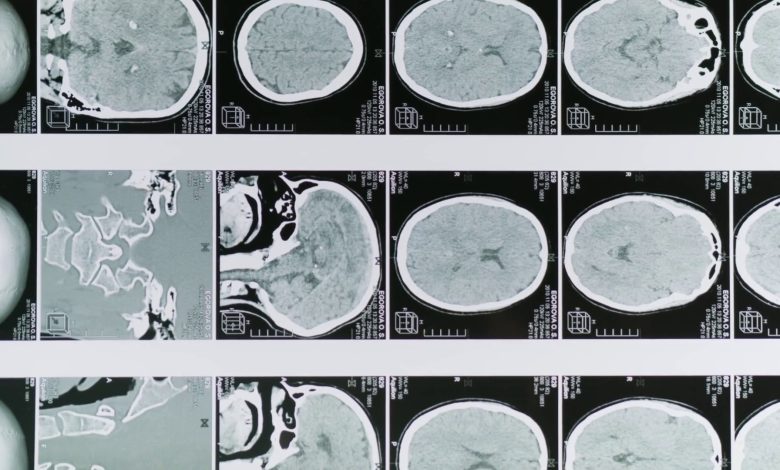

ROMA (ITALPRESS) – Una sperimentazione condotta per la prima volta su un campione di pazienti umani ha rivelato che la combinazione di curcumina e polidatina – due molecole naturali – migliora l’efficacia della terapia chemioterapica nel trattamento del glioblastoma, un tumore cerebrale particolarmente aggressivo. Il test è stato condotto da ricercatori dell’Istituto di farmacologia traslazionale del Consiglio nazionale delle ricerche e della Fondazione per la ricerca di terapie oncologiche integrate, e con la consulenza epidemiologica del Policlinico Gemelli.